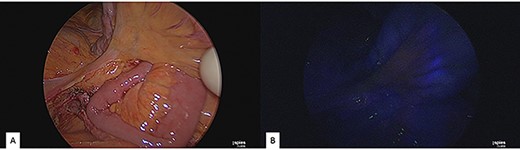

Surgery was performed through a midline laparotomic approach. The superior mesenteric vessels were isolated throughout their course. Jejunal arteries and veins were prepared and dissected. The mass infiltrated the SMA and the SMV saving the first jejunal vessels, right and middle colic vessels. SMA and SMV were temporarily clamped immediately above the lesion. After intravenous administration of indocyanine green, intraoperative near-infrared angiography (KARL STORZ SE & Co, Germany) showed the good vascularization of the small bowel and the right colon (Fig. 2). An en-bloc resection of the tumour and superior mesenteric vessels incorporated in the lesion was performed without vascular reconstruction, preserving the vessels not affected by the neoplasm (Fig. 3).

Intraoperative near-infrared angiography and indocyanine green administration; (A) normal light. (B) Application of near-infrared angiography: notice the good vascularization of the small bowel.